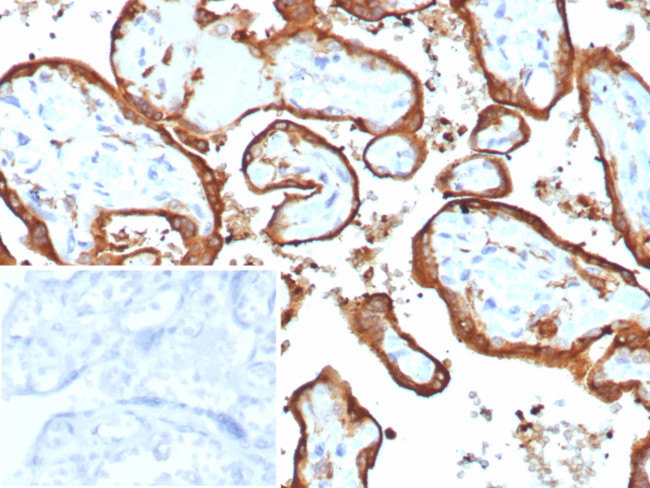

HCG-beta (Pregnancy and Choriocarcinoma Marker) Antibody in Immunohistochemistry (Paraffin) (IHC (P))

HCG-beta (Pregnancy and Choriocarcinoma Marker) Antibody (1081-RBM16-P1ABX) in IHC (P)

Formalin-fixed, paraffin-embedded human placenta stained with HCG-beta Rabbit Recombinant Monoclonal Antibody (HCGa/7806R). Inset: PBS instead of primary antibody; secondary only negative control. {{ $ctrl.currentElement.advancedVerification.fullName }} 验证信息 View more